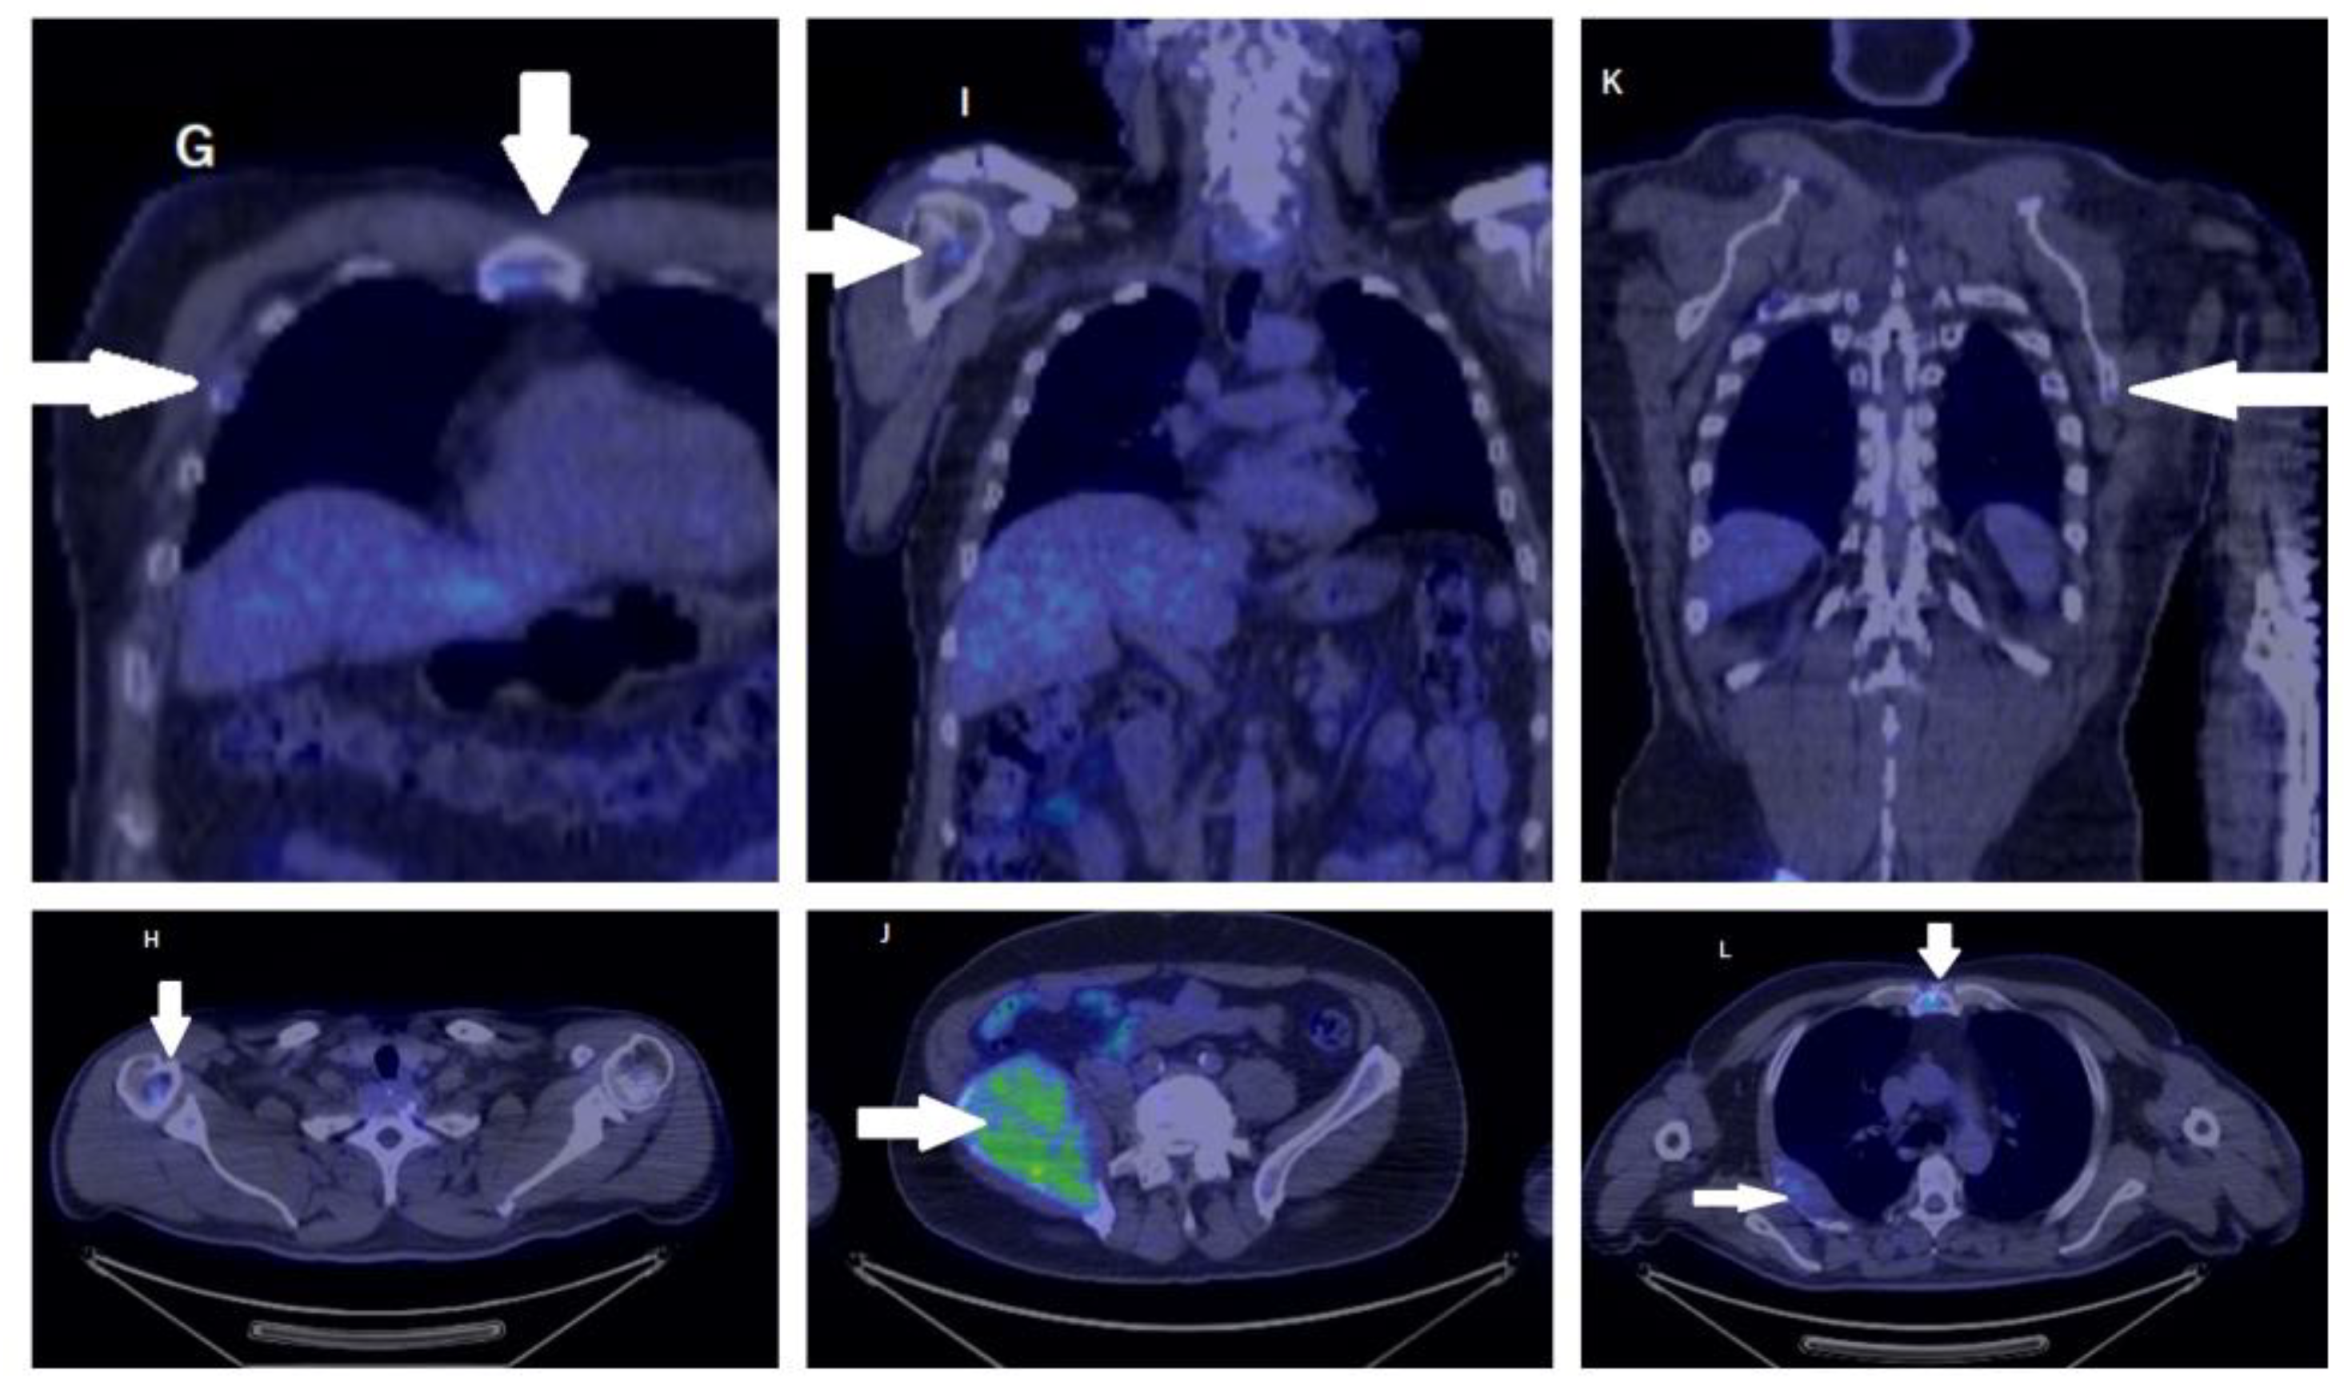

2. Case Report